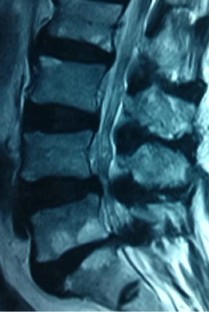

Fig. 1